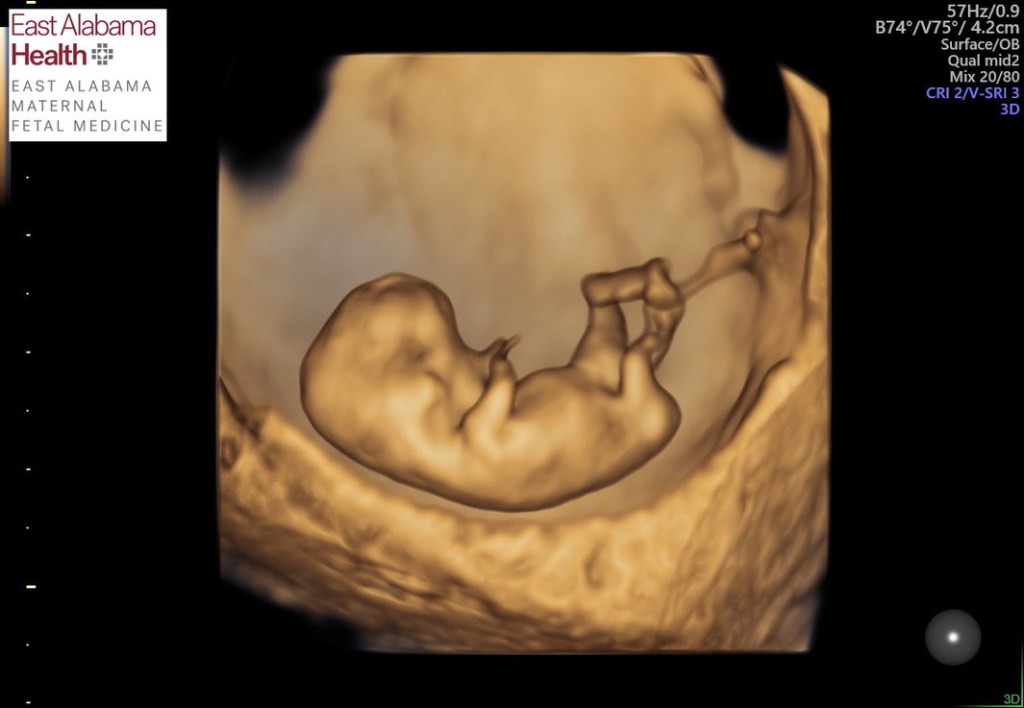

Preparing for Another Girl

I’m 29 weeks along with Addie’s pregnancy. She’s giving me tons of reassurance with constant wiggles and lots of growth. At my growth ultrasound earlier this week, she measured 3lbs 6oz. That’s 1oz bigger than Ginny was when she was born at 35 weeks! We’ve got a lot of hope, but we are also still very much aware of how quickly everything can change. Ideally that awareness makes us appreciate and treasure this special time and doesn’t make us try to protect our hearts in any way. Sometimes trying to protect your heart is the automatic response: don’t think too hard on what you have to lose, don’t get your hopes up. I don’t think that really works when it comes to love; your heart will break no matter how hard you try to protect it. So I try to embrace all I can! Lean in to the love!

I haven’t been the best at that lately. We’ve had a really busy summer which has been fun but distracting. Addie’s “nursery” so far still looks like our guest room but just with a closet full of baby girl clothes and a disassembled crib leaning against the wall. At this point in Chet’s pregnancy, his room was completely ready in his blue and gray beach theme. We have a vision for the nursery – boho rainbows and sunshine with lots of warm creams, golds, and varying shades of salmon pink. Rainbows are a sweet symbol for babies born after loss so it feels special. We have the plan, but are we ready to execute it? Every time I think of putting together the crib and hanging decor, I get excited but also slightly hesitant. I haven’t taken the time to process my emotions about this. I didn’t think this would be a hangup this time around, since we aren’t literally taking down Ginny’s decor to replace it with a new baby’s nursery. Am I afraid of having to take down another nursery that has never been used? Probably, but like I said, I want to lean in. I want to parent Addie as much as I possibly can while I can, even if that means we have to face an unused nursery later. And I obviously want to be ready for her likely arrival home. Yes, the nursery is the next priority.

We are all set when it comes to clothes. We’ve been blessed by wonderful friends who have given us so many cute outfits their girls have outgrown. This is more helpful than these friends even know, because I still have a hard time bringing myself to browse the baby girl sections at stores. We didn’t have to do that with Chet, and now I realize this is another area where I need to take the time to process what I’m feeling. I have lots of memories of picking out adorable clothes for Ginny with my mom and mother-in-law. I found so many sweet floral onesies on sale at Target and Old Navy. I remember washing them with such care in loads of their own, then laying them out on a big clean blanket on the bed so I could carefully hang each one. I kept them as clean and pristine as possible for our precious girl. Little did I know then that they would stay pristine. A week after Ginny’s stillbirth, I angrily pulled those same onesies off the hangers and threw them into piles to give to friends or donate. I remember my mom, sister, and mother in law quietly asking if they could keep a few they purchased as keepsakes. I agreed and kept one or two myself. But mostly it just hurt to think of these clothes waiting in boxes for a sister who may or may not ever appear. We got rid of almost everything. So I was grateful to receive clothes that have already been worn and loved; there are even a few that I recognize that we had for Ginny. As seems fitting for a 3rd child, I was not nearly as gentle with Addie’s clothes. I washed them with our other clothes and sorted them on the floor while Chet rummaged through them. It does feel good to see a closet full of pink and white outfits with matching bloomers and bows. Ginny will actually get that little sister whom I didn’t dare hope for. Thank you, Lord.

Daniel, Chet, and I are all really happy to be having a girl. Every time we asked Chet if he wanted a baby brother or sister, he would respond, “Baby SEEEEESTER!” No one could or would ever replace Ginny, but Daniel and I both had already pictured ourselves raising a daughter. I saw myself as a girl mom and a boy mom, but the world could only see me as a boy mom. Having another girl will change that. I am so looking forward to craft, shop, and chat with Addie as she grows up (Not that Chet won’t do those things; but considering how much he already loves cars, I think he’ll have other interests haha). So when I got the phone call from the nurse with the results from the genetic testing, I immediately started crying tears of joy when she said “female”. I couldn’t wait to relay the news to Daniel. I considered showing up to his office with a balloon saying “It’s a GIRL”. But ultimately I couldn’t wait that long and knew he couldn’t either. I called him up, and he had the same reaction I did! Having another girl feels like God is handing us such a kind and generous gift.

As I gaze at Addie’s ultrasound pictures, I find myself daydreaming about holding her, feeding her, and watching Chet and Daniel love on her. My heart is so full already. Now we need to spend the next 10ish weeks preparing the nursery, preparing Chet, and remembering Ginny as we embrace all we can of this pregnancy in hopes of bringing little sister home.